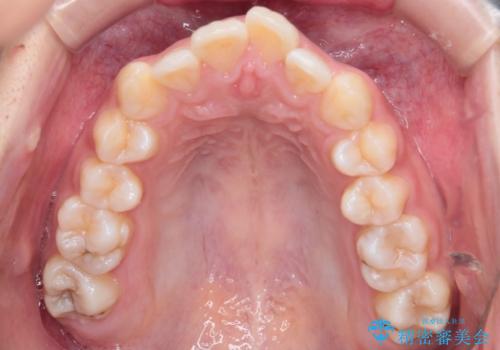

- 前歯から奥歯にかけて歯の重なりが激しい歯のがたつき(重度叢生)を主訴にご来院されました。精密検査の結果、歯が並ぶスペースが大幅に不足しており、歯並びを整え、口元を美しく引っ込めるためには、スペースの確保が必要と診断しました。そこで、上下左右の第一小臼歯(4番目の歯)を計4本抜歯し、そのスペースを利用して歯並び全体を整える抜歯矯正の治療計画を立案。装置には、透明で目立たないインビザラインを採用し、審美性と治療効果の両立を目指しました。

今回の治療では、重度の叢生を改善するため、まず計画通り上下左右4本の小臼歯を抜歯し、歯を並べるための十分なスペースを確保しました。装置には透明で取り外し可能なインビザラインを使用。抜歯によってできたスペースを最大限に活用し、マウスピースを定期的に交換しながら、デコボコを解消しつつ、前歯を効果的に後退させました。

治療の結果、長年の悩みであった重度の歯のがたつきが解消され、口元の突出感も改善。機能的にも安定し、審美的にも美しい、理想的な歯並びを獲得していただけました。